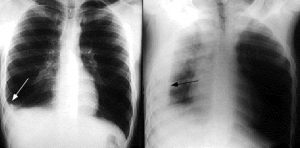

Hình ảnh Xquang bệnh nhân tràn dịch màng phổi phải

Hiện nay, để chẩn đoán xác định tràn dịch màng phổi, các bác sĩ sẽ dựa trên kết quả khám lâm sàng kết hợp các phương pháp cận lâm sàng như chụp Xquang, chụp cắt lớp vi tính lồng ngực và soi màng phổi.